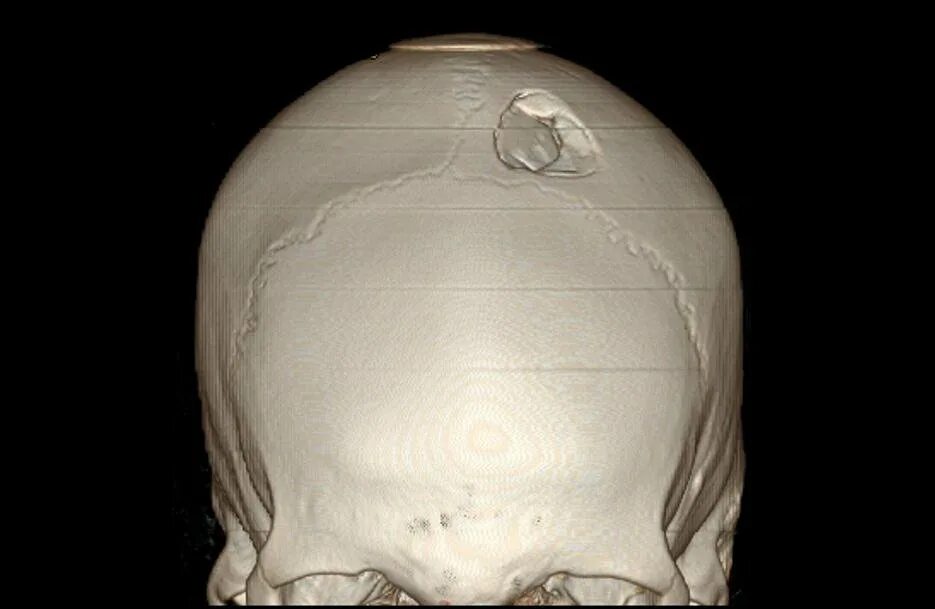

Оскольчатый перелом черепа